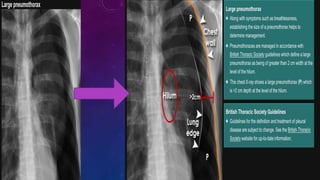

• CXR shows the sharply defined edge of the deflated lung with a complete lack of

lung markings between this and the chest wall.

• CXR also shows any mediastinal displacement and gives information regarding the

presence or absence of pleural fluid and underlying pulmonary disease.